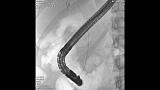

Здравствуйте. Пациентка, 32 года. Поступила на хирургическое отделение с диагнозом ЖКБ: холедохолитиаз. По данным МРТ: ЖКБ, множественные мелкие конкременты холедоха. При дуоденоскопии выявлено наличие вклиненного конкремента большого дуоденального сосочка. Выполнена прекатсфинктеротомия, получено 3 конкремента, диаметром около 0.4-0.5 см. Далее канюляция холедоха проволочным папиллотомом, выявлены многочисленные конкременты холедоха. Выполнена литоэкстракция ревизионным баллоном (на последнем фото окклюзионная холангиография - в просвете холедоха не конкременты, а пузырьки воздуха)).